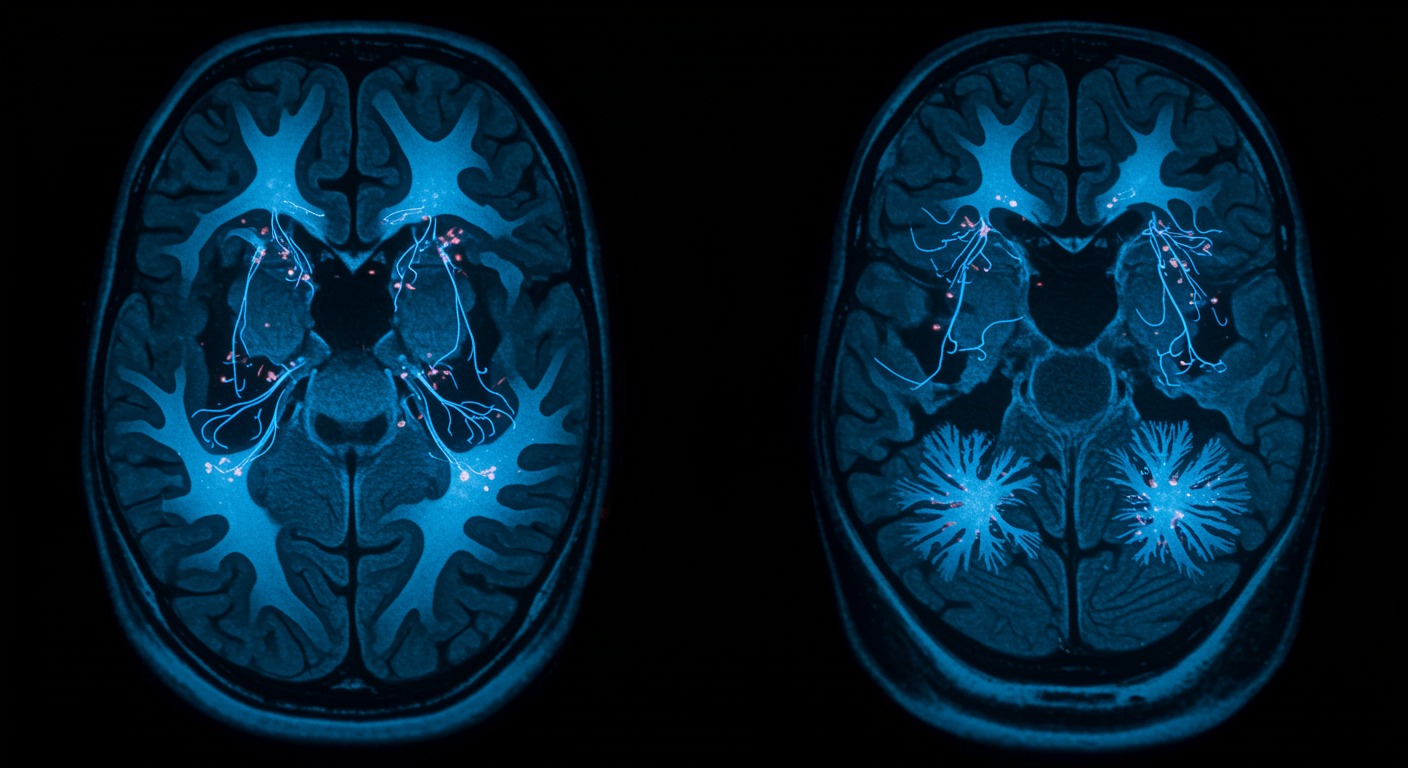

Neuroimaging studies consistently demonstrate that loneliness alters brain activity and structure across multiple networks. The “social brain” - including regions like the anterior cingulate cortex, insula, and temporoparietal junction - shows altered connectivity patterns in lonely individuals. These changes affect how the brain processes social information, regulates emotions, and responds to stress.

Loneliness activates the brain’s threat detection systems while suppressing social reward circuits. The anterior cingulate cortex becomes hyperactive to social threats, while the ventral striatum shows reduced response to social rewards. This creates a neurobiological state of hypervigilance combined with reduced motivation for social connection - a pattern that can become self-perpetuating.

Key findings from loneliness neuroscience research:

- Increased amygdala reactivity to social threats in lonely individuals

- Reduced prefrontal cortex activity during social cognition tasks

- Altered default mode network connectivity affecting self-referential thinking

- Decreased social reward network activity reducing motivation for connection

- Structural brain changes in regions involved in social processing with chronic loneliness